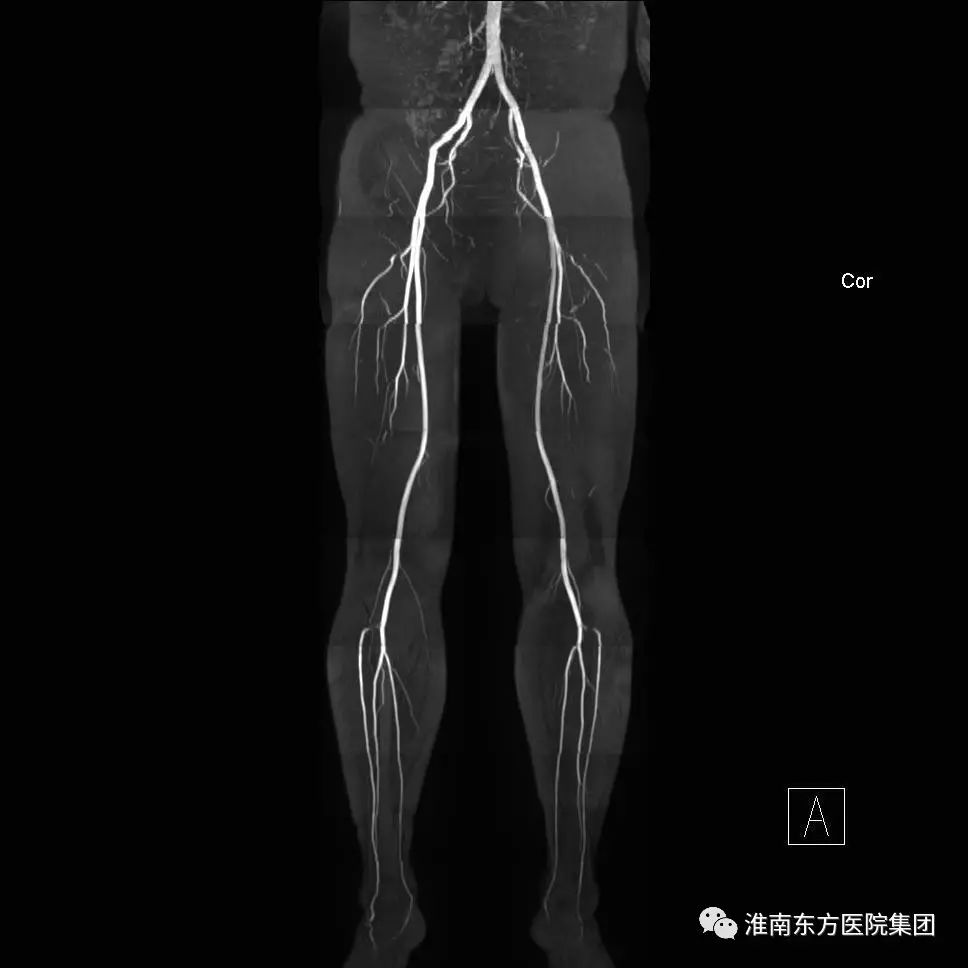

下肢动脉

三、36通道的下肢血管线圈使大范围的下肢动静脉血管不用打药、一次性成像成为现实。